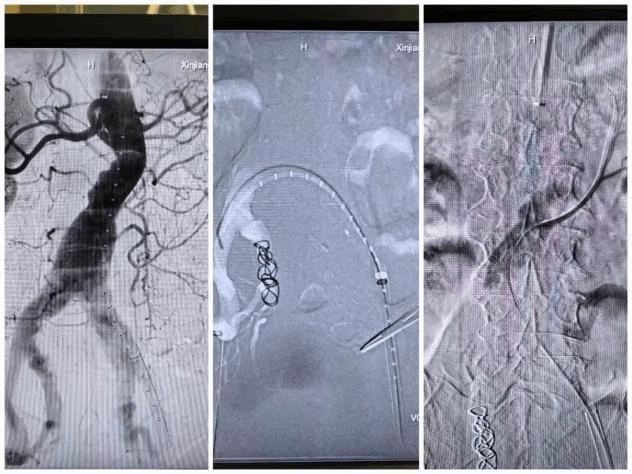

手术当天,在麻醉科团队和手术室专业护理组的细心配合下,手术团队顺利完成了“腹主动脉覆膜支架腔内隔绝术+腹主动脉开窗分支覆膜支架置入术(左肾副肾动脉及左侧髂内动脉)+腹主动脉分支覆膜支架置入术+经导管内髂内动脉栓塞术+腹主动脉造影+腹主动脉球囊血管成形术”,术后经造影检查,提示手术成形效果好,各分支动脉血流通畅,腹主动脉瘤成功隔绝,右髂内动脉成功栓塞,避免了内漏发生。术后在呼吸重症医学中心团队的精心监护下,患者很快转回普通病房,并顺利康复出院。整个诊疗过程中多学科医护人员精密合作,克服了重重困难,为患者的安全和健康全力以赴。